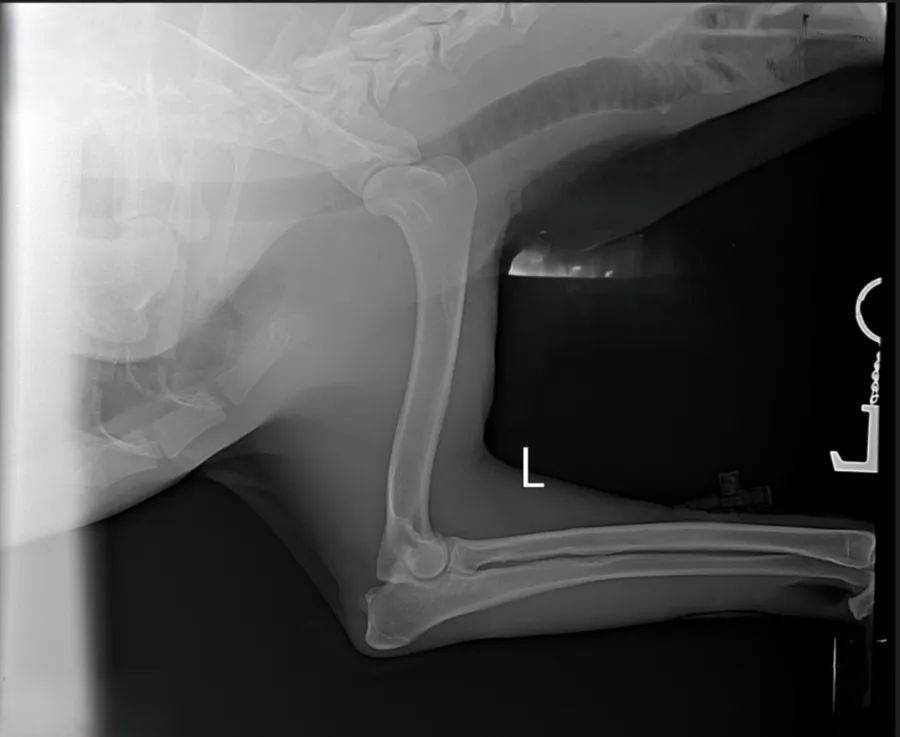

Единственным надёжным методом подтверждения является рентгенография тазобедренных суставов, проведённая опытным специалистом. Важно правильно уложить собаку под наркозом, поскольку неправильная позиция может исказить результаты исследования.

Для определения степени тяжести дисплазии используют международную классификацию FCI/РКФ:

- А — норма.

- B — лёгкое отклонение, допустимое для разведения.

- C — средняя степень отклонения.

- D — тяжелая форма, противопоказанная для размножения.

- E — крайне тяжёлая патология, показывающая полную невозможность нормальной жизнедеятельности.